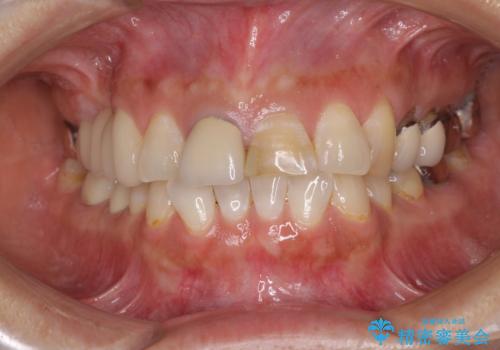

- 上の前歯2本が不調和であることを気にして来院された患者様です。

以前に前歯をぶつけた際、一方は神経を取り除いたためクラウンを装着し、もう一方は神経が残せたため一部修復をしていたとのことでした。

神経は残せていましたが、歯の色の変色が著しく、また広がった大きな形をしていたため、前歯2本をオールセラミッククラウンにて補綴することとしました。